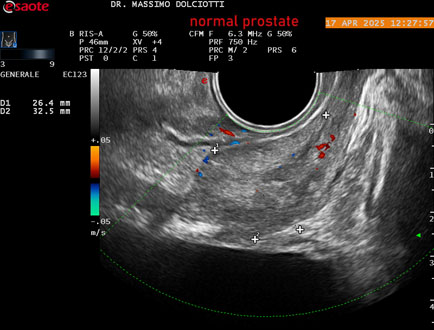

Data inserimento: 01/10/2025

Ecografia del: 17/04/2025

Strumento: Esaote MyLab Eight

Sonda: Convex Multifrequenza 1-8 MHz, Endocavitaria Multifrequenza 3-9 MHz e 3-13 MHz

Età Paziente: M 35 anni

Motivazione dell'esame: disuria.

Commento all'esame: le immagini ed il video documentano la prostata di ecostruttura regolare e morfovolumetria normale con diametro trasversale di 40 mm, diametro anteroposteriore di 21 mm e diametro longitudinale di 43 mm, con volume prostatico calcolato di 18 cc (v.n. < 20 cc), il profilo prostatico è regolare e netto, non si documentano calcificazioni intraghiandolari, la vascolarizzazione della ghiandola è normale. La vescicola seminale destra presenta diametro longitudinale di 44,4 x 7,8 mm, la vescicale seminale sinistra ha diametro longitudinale di 45,3 mm x 7,2 mm.

Conclusioni: prostata normale (normal prostate).

Presentazione: Dr. Massimo Dolciotti - Ancona

Elaborazione digitale: Andrea Dini - Ancona